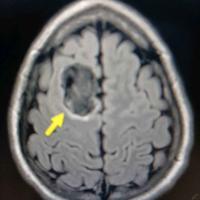

发现颅内占位5天,脑膜瘤?

发现颅内占位5天,脑膜瘤?...

由 medjpg 发表于 2026-03-24 22:32